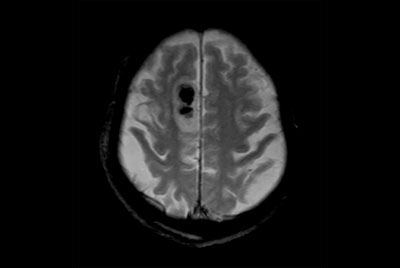

Brain infarction

Brain small infarction

Brain overview

Comprehensive Brain imaging at 1.5T

Comprehensive Brain imaging at 3.0T